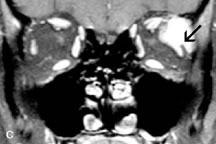

Cavernous hemangiomas appear as well-circumscribed, smooth, usually intraconal masses that are isointense to muscle on T1-weighted images and hyperintense on T2-weighted images (Fig. 12). Patchy early enhancement is typically followed by diffuse, more homogeneous enhancement.39 The internal architecture of the mass, including septation and internal vasculature, may often be appreciated with high-quality orbital imaging.40

Fig. 12. A. T1- and (B) T2-weighted MR scans demonstrate a well-circumscribed intraconal mass causing severe optic nerve displacement. These lesions are usually intermediate in signal intensity on T1-weighted scans and very hyperintense on T2-weighted Images. C and D. Postcontrast fat-suppressed T1-weighted scans demonstrate characteristic patchy intense enhancement that becomes more complete from the initial postcontrast scan (C) to a more delayed scan (D).